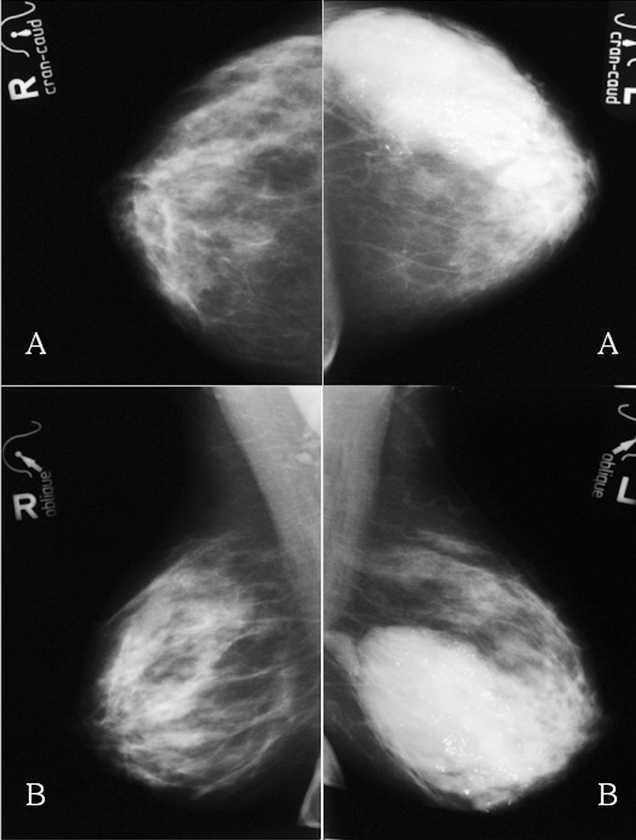

Antes de realizar la biopsia de ambas mamas, se realizó una mamografía, una ecografía y una resonancia magnética bilateral (figs. 1-4). Tras obtener y analizar las imágenes, se procedió a una punción con aguja gruesa, tanto del nódulo en el CSE de la MD como del área de aumento de densidad en los cuadrantes externos de la MI. El nódulo de la MD se describió como CDI (fig. 5) y la biopsia de la MI informó de la presencia de áreas de CLI (fig. 6). Los receptores de estrógenos (RE) y de progesterona (RP) eran negativos en la MD y el tumor no sobreexpresaba la proteína Her2. El tumor de la MI presentaba RE (+), RP () y sobreexpresaba Her2. Se realizó un estudio de extensión que fue negativo para lesiones metastásicas.

Figura 1. Mamografías bilaterales iniciales. A: proyección craneocaudal. B: proyección oblicua. Mama derecha: masa de 6 cm de diámetro con algunos márgenes especulados. Mama izquierda: masa polilobulada con márgenes redondeados y especulados, y numerosas microcalcificaciones (flechas negras).